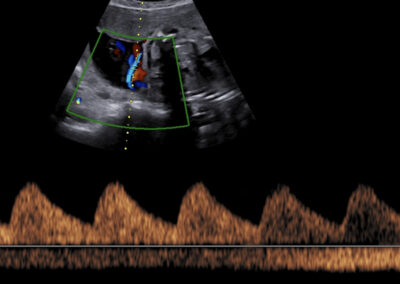

Genetický ultrazvuk Fetální echokardiografie Dopplerovské vyšetření krevního oběhu miminka a placenty Screening předčasného porodu Screening preeklampsie a zaostávání růstu miminka Vyšetření vícečetných těhotenství 3D-4D ultrazvuk Určení pohlaví miminka